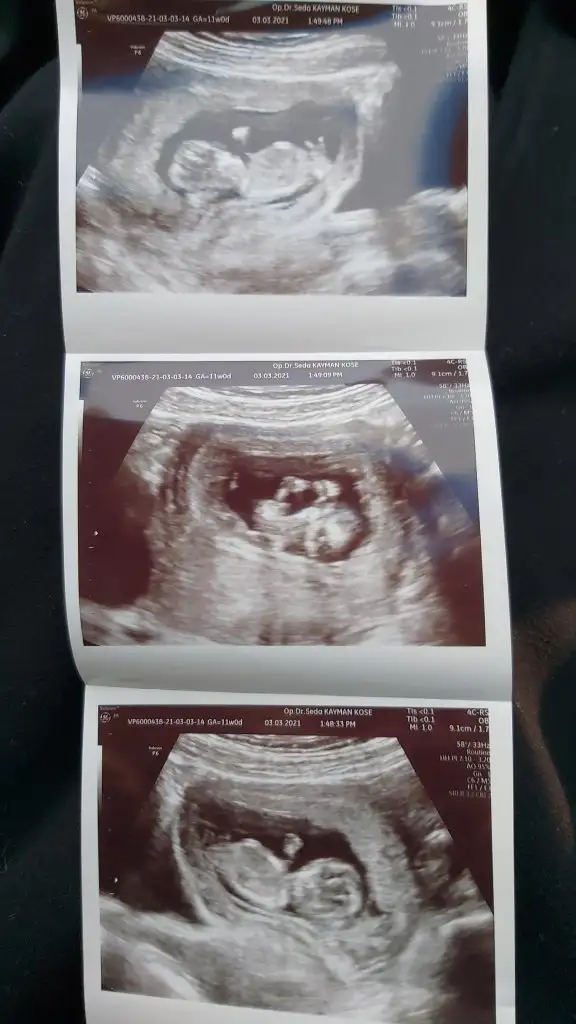

bizim hakkımızdaki tahminin nedir? 11+1 idi ama ultrasonda 11+4 çıktı ancak doktor emin olmadıgı için söyleyemedi cinsiyeti :)